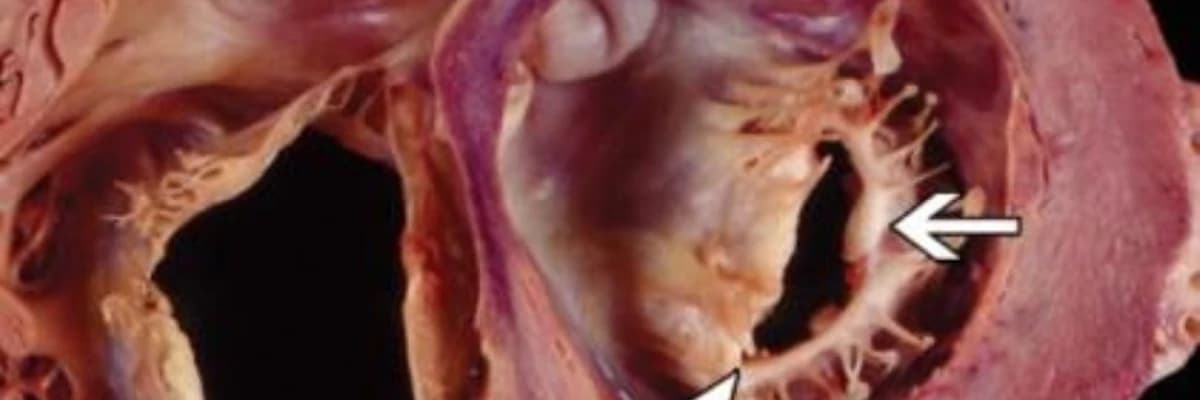

| Cərrahi Müdaxilə | Ürək qapaqlarının ciddi zədələnməsi halında qapaqların təmiri və ya dəyişdirilməsi əməliyyatları. |